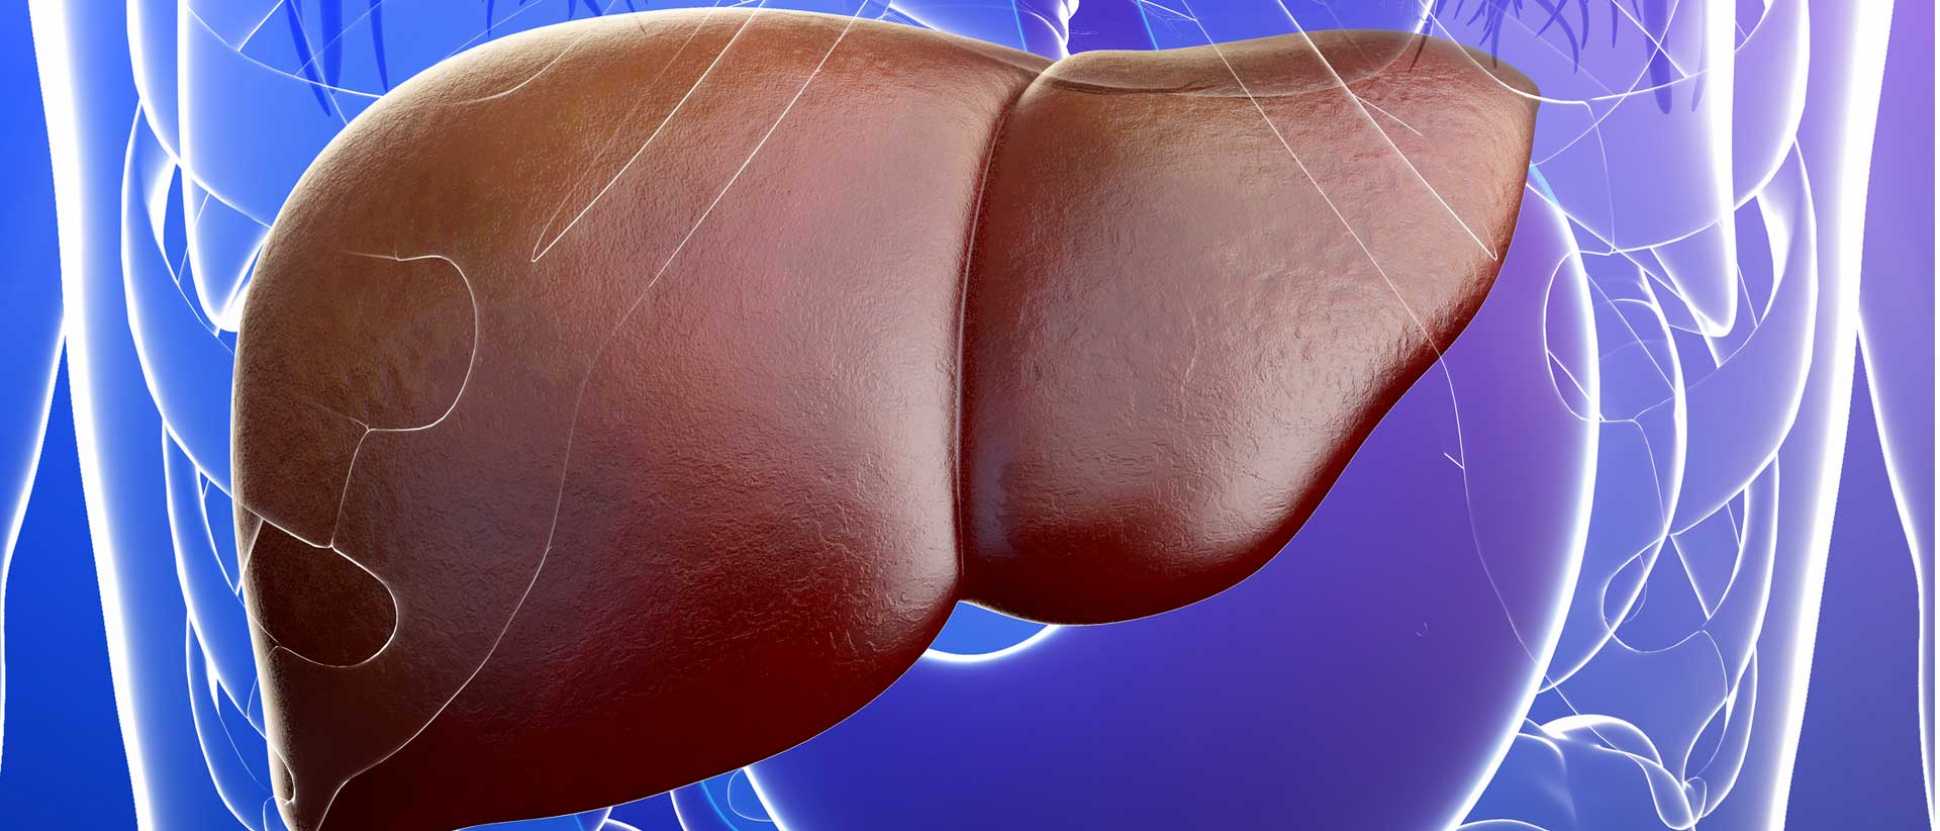

В последние годы в социальных сетях и блогах все чаще встречается необычное явление, известное как “Печень фото”. Этот термин относится к художественному стилю, при котором фотографии печени человека становятся объектом эстетического восприятия и даже искусства. Такие изображения, часто с высоким разрешением и детальной проработкой текстур, привлекают внимание не только медиков и исследователей, но и широкой публики, вызывая удивление и восхищение своей красотой и уникальностью.

Печень фото